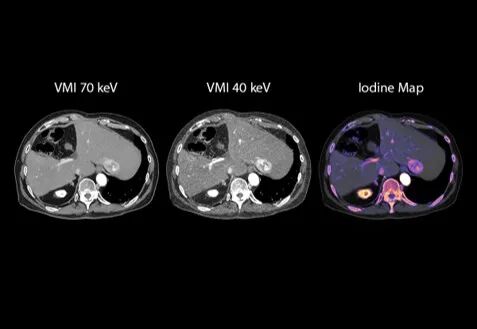

🔹在肿瘤评估中,基于CZT-PCCT的能谱成像能力,可提供虚拟单能量图像及碘图等多维定量信息,有助于更清晰地呈现病灶强化特征与组织差异。相较传统成像方式,可以为肿瘤的检出、定性及评估提供更加丰富的影像参考。